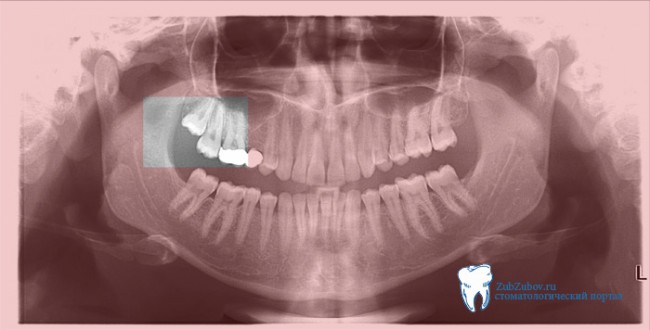

Зубы Мудрости Симптомы Фото

Зубы Мудрости Симптомы Фото 111 фотографий